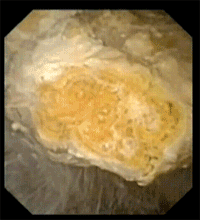

640 1.gif

优路自由星?击石粉末化效果动图

光纤铥激光高水吸收系数的物理特性让他们思考如何应用在结石手术中,经过研发团队的不断努力,去年他们推出了一款碎石激光——优路自由星?超脉冲光纤铥激光,可以做到原位、超粉碎石,常规粉末化的标准在2mm以下,优路自由星?粉末化程度则可以达到1mm以下,甚至0.2mm。